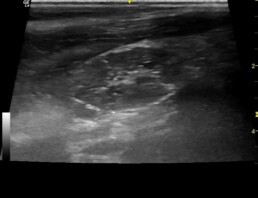

Zudem lag ein geringgradiger Perikarderguss (Abb. 5) und zudem sonographisch vergrößerte Buglymphknoten vor (Abb. 6).

Abb. 5: RKRA- ggr. Perikarderguss (Pfeil)

Abb. 6: Darstellung Buglymphknoten rechts